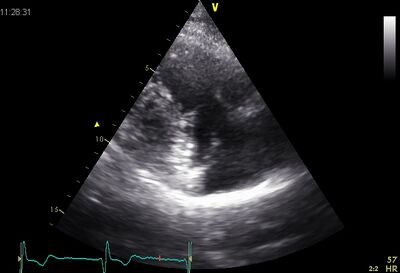

Echocardiographic views

Ap4ch.jpg Subcostaal4ch03.jpg

AP4CH Subcostal